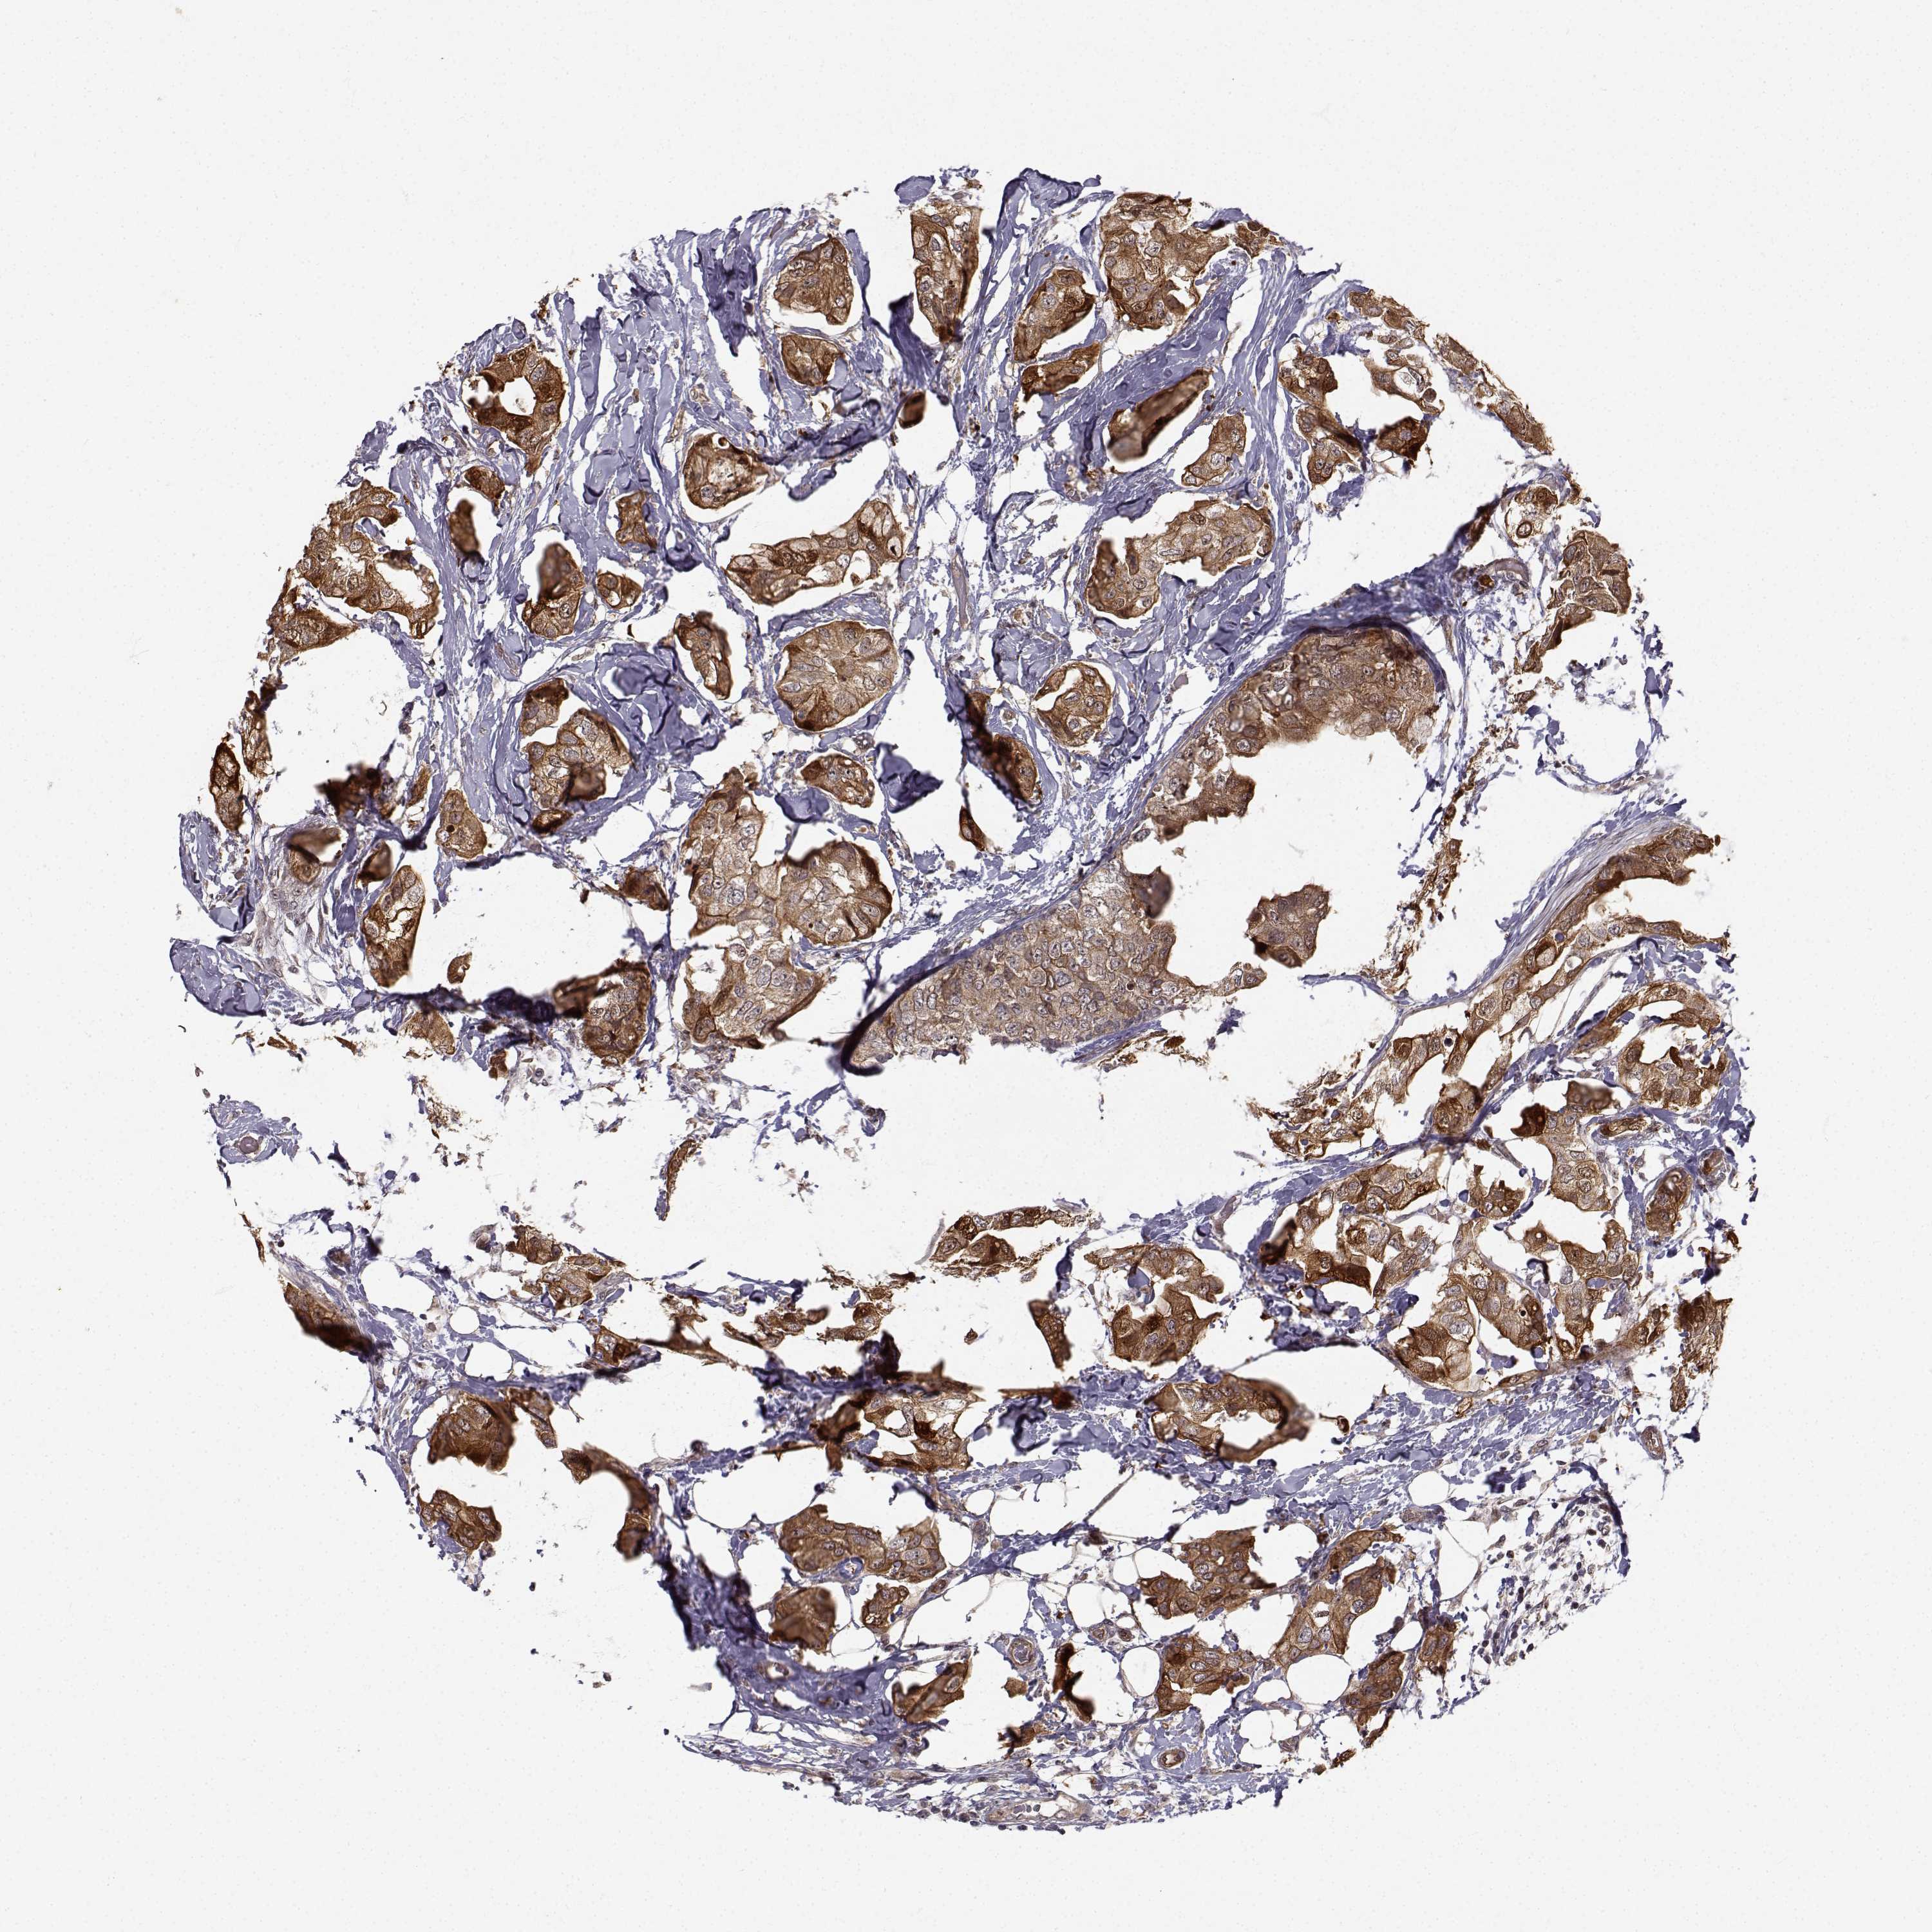

CANCER BREAST CANCER Show tissue menu

BRCA TCGA BRCA VALIDATION PROTEIN EXPRESSION

Breast cancer

Human cancer